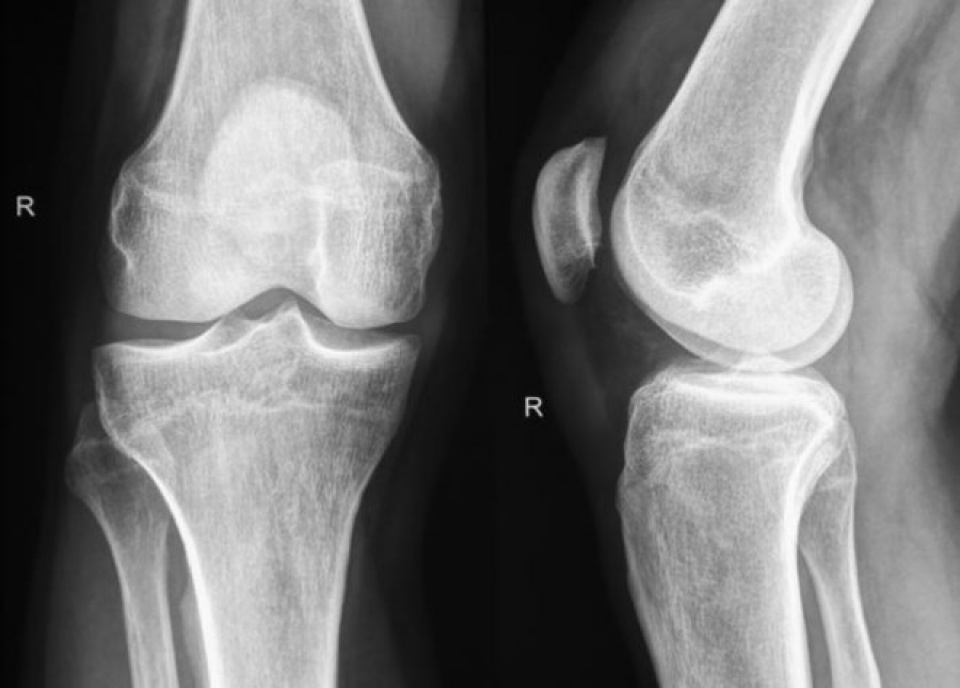

| Kỹ thuật can thiệp tế bào để cơ thể người tự tái tạo các bộ phận hư hỏng đánh dấu bước nhảy vọt trong nghiên cứu công nghệ tái tạo sinh học. (Nguồn: Medical News Today) |